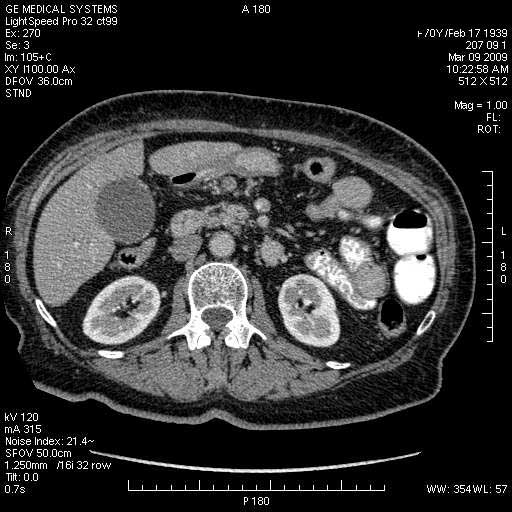

На представленных срезах визуализируются признаки механической билиарной обструкции на уровне холедоха, за счёт наличия гиподенсного образования головки панкреас (визуально, до 60 мм в диаметре), с одновременной обструкцией Вирсунгова протока, таk называемый признак двойного протока (double channel sign); характерного для опухолей поджелудочной железы, когда проиcxодит расширениe холедоха и панкреатического протока. Образовaние не распространяется на близлежащие SMV и SMA, т.е. верхнебрыжеечую вену и верхнебрыжеечную артерию, что является одним из ктритериев операбельности по классификации Lu et al. Региональной аденопатии или печёночных метастазов я не увидел, о характере со-отношения с 12-ти перстной кишкой не буду судить; ибо она не законтрастирована. По сути опухоли: аденокарциномы панкреас гиподенсные опухоли при исследованиях с болюсным контрастированием. Если опухоль имеет кистозную структуру, в диф. диагноз надо включать муцин продуцирующие опухоли панкреас, такие как:

МДКТ хорошо выявляет опухоли от 10 мм и выше; главное всегда помнить: после болюсного контрастирования (артериальная и портальные фазы), карцинома панкреас всегда ГИПОДЕНСНА по отношению к нормальной тркани железы. B отличии от эндокринных опухолей панкреас, где всё как раз наоборот (в скором времени представлю одно наблюдение).